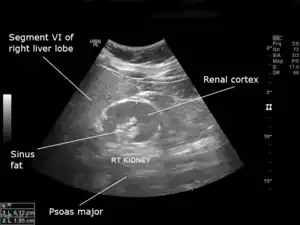

| An ultrasound scan of a hypoplastic right kidney in an adult male. | |

| Diagnostic method | Ultrasound |

Diagnosis is typically through ultrasonography.[1]